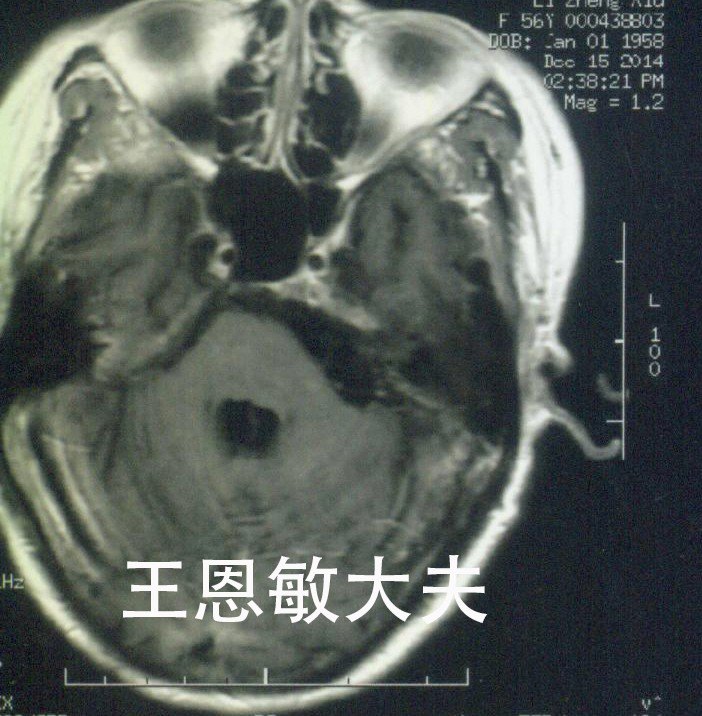

复发听神经瘤的射波刀治疗--每周一例